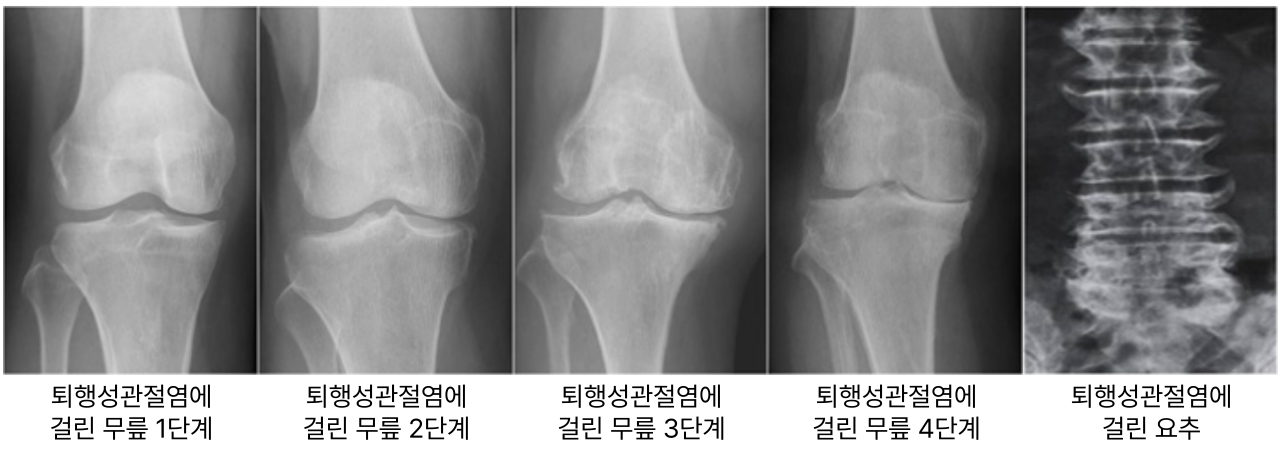

대부분 문진과 진찰로 어렵지 않게 진단할 수 있으며, 엑스레이 검사를 통해 확진합니다.